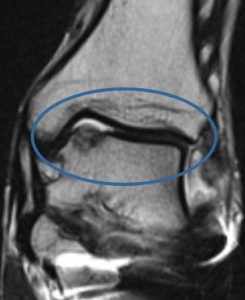

La RMN (risonanza magnetica) permette di valutare conflitto correlato alla presenza di tessuto fibro-sinoviale “esuberante” in eccesso oltre alle lesioni legamentose e cartilaginee frequentemente associate.

Alcuni autori hanno riscontrato un bassa affidabilità diagnostica della risonanza magnetica nella diagnosi di Sindrome da impingement “fibroso”.

Con il termine sindromi da conflitto o da impingement tibio-tarsico si designa essenzialmente un gruppo di condizioni patologiche molto frequenti nello sport. Esse possono essere correlate a esiti di traumi distorsivi o a sovraccarico funzionale a tale livello. Sintomi e segni clinici possono mimare una varietà di quadri patologici e una diagnosi accurata è spesso difficile e la terapia conseguente ritardata. Tuttavia, la diagnostica per immagini ed in particolar modo la Risonanza Magnetica (RM) può risultare utile ai fini della diagnosi.

Il trattamento conservativo porta alla guarigione senza complicanze nella maggior parte dei casi; tuttavia si è stimato che circa il 3% delle distorsioni di caviglia può portare ad una sindrome da impingement antero-laterale. Un trauma in inversione con almeno una lesione parziale del legamento talo-fibulare anteriore può determinare un danno con conseguente reazione infiammatoria della sinovia a livello dell’interlinea articolare antero-laterale. In assenza di un adeguato trattamento di immobilizzazione o di riabilitazione, può aversi ipertrofia e fibrosi cicatriziale a livello della sinovia. La cronicizzazione di questi fenomeni può portare allo sviluppo di una proliferazione che si estende nel recesso antero-laterale e che causa impingement meccanico e dolore. Più raramente questa massa può determinare l’erosione della porzione antero-laterale del domo astragalico, con conseguente sviluppo di foci di condromalacia. Oltre all’ispessimento ed alla deformità cicatriziale del legamento tibio-fibulare anteriore, la RM eseguita su piani di scansione assiali e sagittali, mostra, soprattutto in presenza di versamento intra-articolare, un’intensità di segnale intermedia del tessuto sinoviale sia nelle sequenze T1 che T2 pesate . RM ed artro-RM, soprattutto in presenza di versamento intra-articolare, sono in grado di documentare sia l’ipertrofia sinoviale, causa di impingement antero-laterale, che eventuali lesioni cartilaginee, ossee e legamentose associate.

c) La sindrome da impingement posteriore, tipica dei danzatori e dei ginnasti, è di solito determinata dalla presenza di un os trigonum o da un tubercolo posteriore dell’astragalo prominente che determinano una reazione infiammatoria sinoviale a tale livello. Ci sono, comunque, altre cause ossee e dei tessuti molli, che giustificano il termine generico di impingement posteriore di caviglia. All’esame obiettivo si hanno dolore durante la flessione plantare passiva e dolorabilità alla palpazione della porzione posteriore della caviglia con possibile limitazione alla flessione plantare. Queste alterazioni sinoviali sono ben dimostrabili all’esame RM che mostra la distensione di queste strutture sinoviali, dovuta alla presenza di versamento, documentato da una tipica iperintensità di segnale nelle sequenze T2 pesate e ipointensità nelle sequenze T1 pesate; anche le cause di impingement sono dimostrate con questa tecnica .

La RM è in grado inoltre di porre una diagnosi differenziale con un’ampia varietà di cause determinanti una sindrome dolorosa posteriore di caviglia, che clinicamente può mimare la sindrome da impingement posteriore. Tra queste sono incluse: lesioni del tendine d’Achille, borsiti retro-calcaneale, tenosinovite del tendine flessore lungo dell’alluce, artrite tibio-talare o sottoastragalica, lesioni osteocondrali, sindrome del tunnel tarsale, instabilità post-traumatica, distrazioni o sublussazioni dei tendini peronieri.